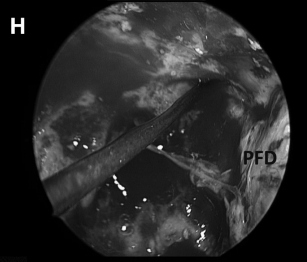

▼(H)术野侧面、后面方向为面神经所在。

▼(L)使用鼻中隔瓣 (NSF)完成封闭。CC,囊包膜;PFD,后颅窝硬脑膜;S,蝶鞍;T,肿瘤。